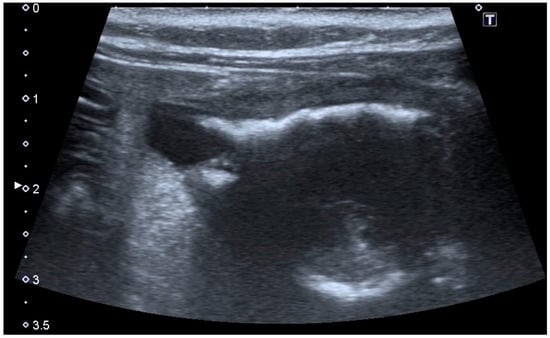

Extramural vesicourachal diverticulum was diagnosed in 20.0% of cats and 18.4% of dogs. Four out of 19 were of large dimensions and extended 1 to 2 cm cranially to the serosa of the urinary bladder apex; 3/19 appeared 0.5–1 cm in diameter, while 12/19 were smaller than 0.5 cm. The wall appeared as a thin hyperechoic line and the content was similar to that of the bladder (Figure 3).

Figure 3. Longitudinal ultrasound image of the urinary bladder in a cat, showing the presence of a small (<1 cm diameter), well-defined, fluid-filled, anechoic structure, protruding beyond the serosal surface of the cranioventral bladder wall, consistent with extramural vesicourachal diverticulum. The bladder presents a moderate, diffuse, thickening of the wall, with an irregular mucosal surface. A moderate amount of echogenic sediment is present in the lumen. Shadowing hyperechoic material adhered to the ventral bladder wall mucosa is also observed, which may represent congealed mineralized sediment.